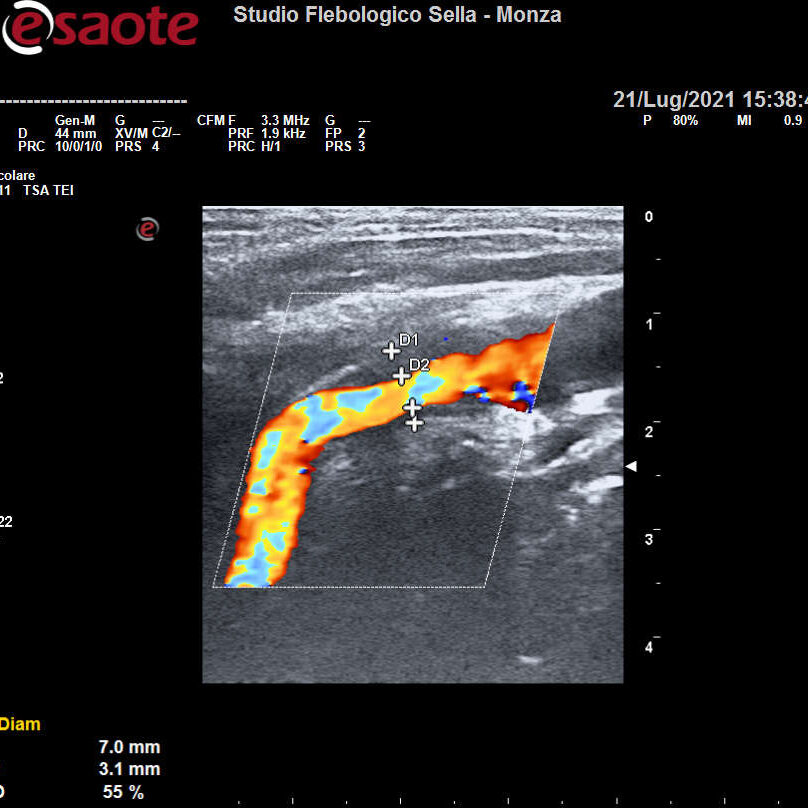

Abbiamo precedentemente visto come l’intuizione del fisico austriaco Christian Doppler ha posto le basi teoriche per la nascita dell’EcocolorDoppler. La deformazione degli ultrasuoni nell’attraversare il corpo umano consente la ricostruzione in immagini dei tessuti, vasi compresi. Otteniamo quindi informazioni sulla forma e il decorso dei distretti vascolari esplorati e sulla velocità del sangue contenuto. Un utile campo applicativo è rappresentato dall’EcocolorDoppler dei tronchi sovraortici ossia lo studio delle arterie del collo. Il precoce riscontro di problemi a carico di carotidi e vertebrali ne previene infatti una grave complicanza: l’ictus ischemico.